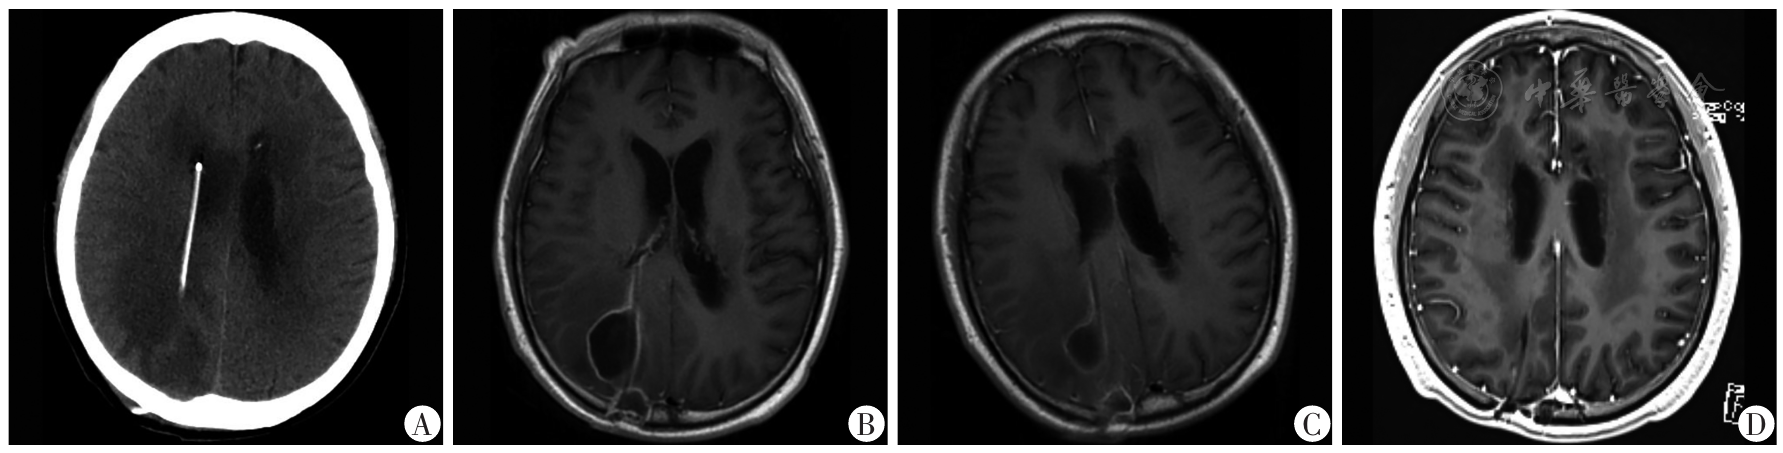

图1 脑室-腹腔分流术后脑脓肿患者的头部影像学资料A:入院时头部CT示分流管周围见多发低密度影;B:入院后3 d头部MRI增强示分流管周围多发环状强化灶;C:抗感染治疗2周后复查头部MRI增强示分流管周围环形强化灶缩小;D:出院后半年随访复查头部MRI增强示分流管周围强化灶消失

Fig.1 Head imaging data of patients with brain abscess after ventriculo-peritoneal shunt surgery